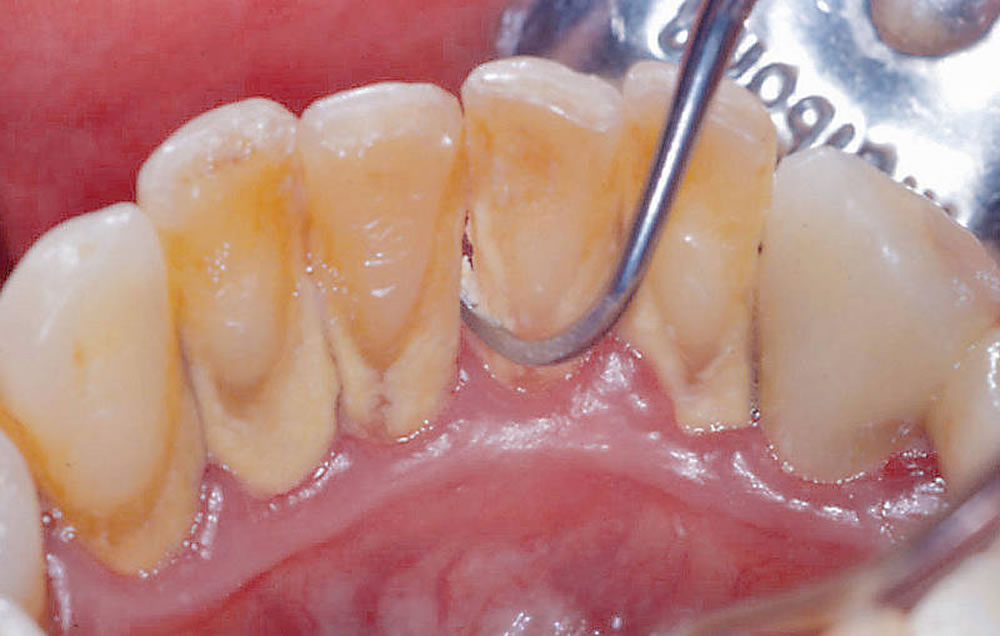

スケーリング

歯面や歯間に付着した歯垢・歯石をスケーラーという器具で除去します。当院では、短時間で広範囲の処置が行える超音波スケーラーと細部の処置に向いているハンドスケーラーを使い分け、精密なスケーリングを実施いたします。